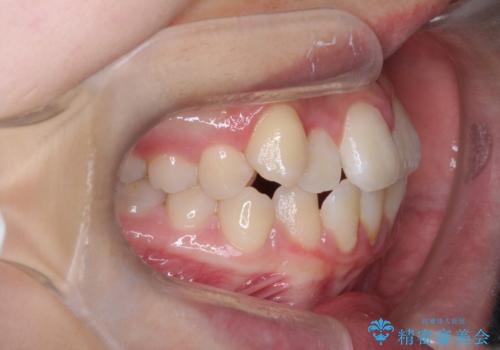

- 八重歯を主訴に来院されました。

左側犬歯が埋伏していましたが、第一小臼歯(4番目の歯)を抜歯したことでできたスペースに牽引し、右側の飛び出した八重歯を含め、歯全体を整列することができ患者様も満足していただきました。